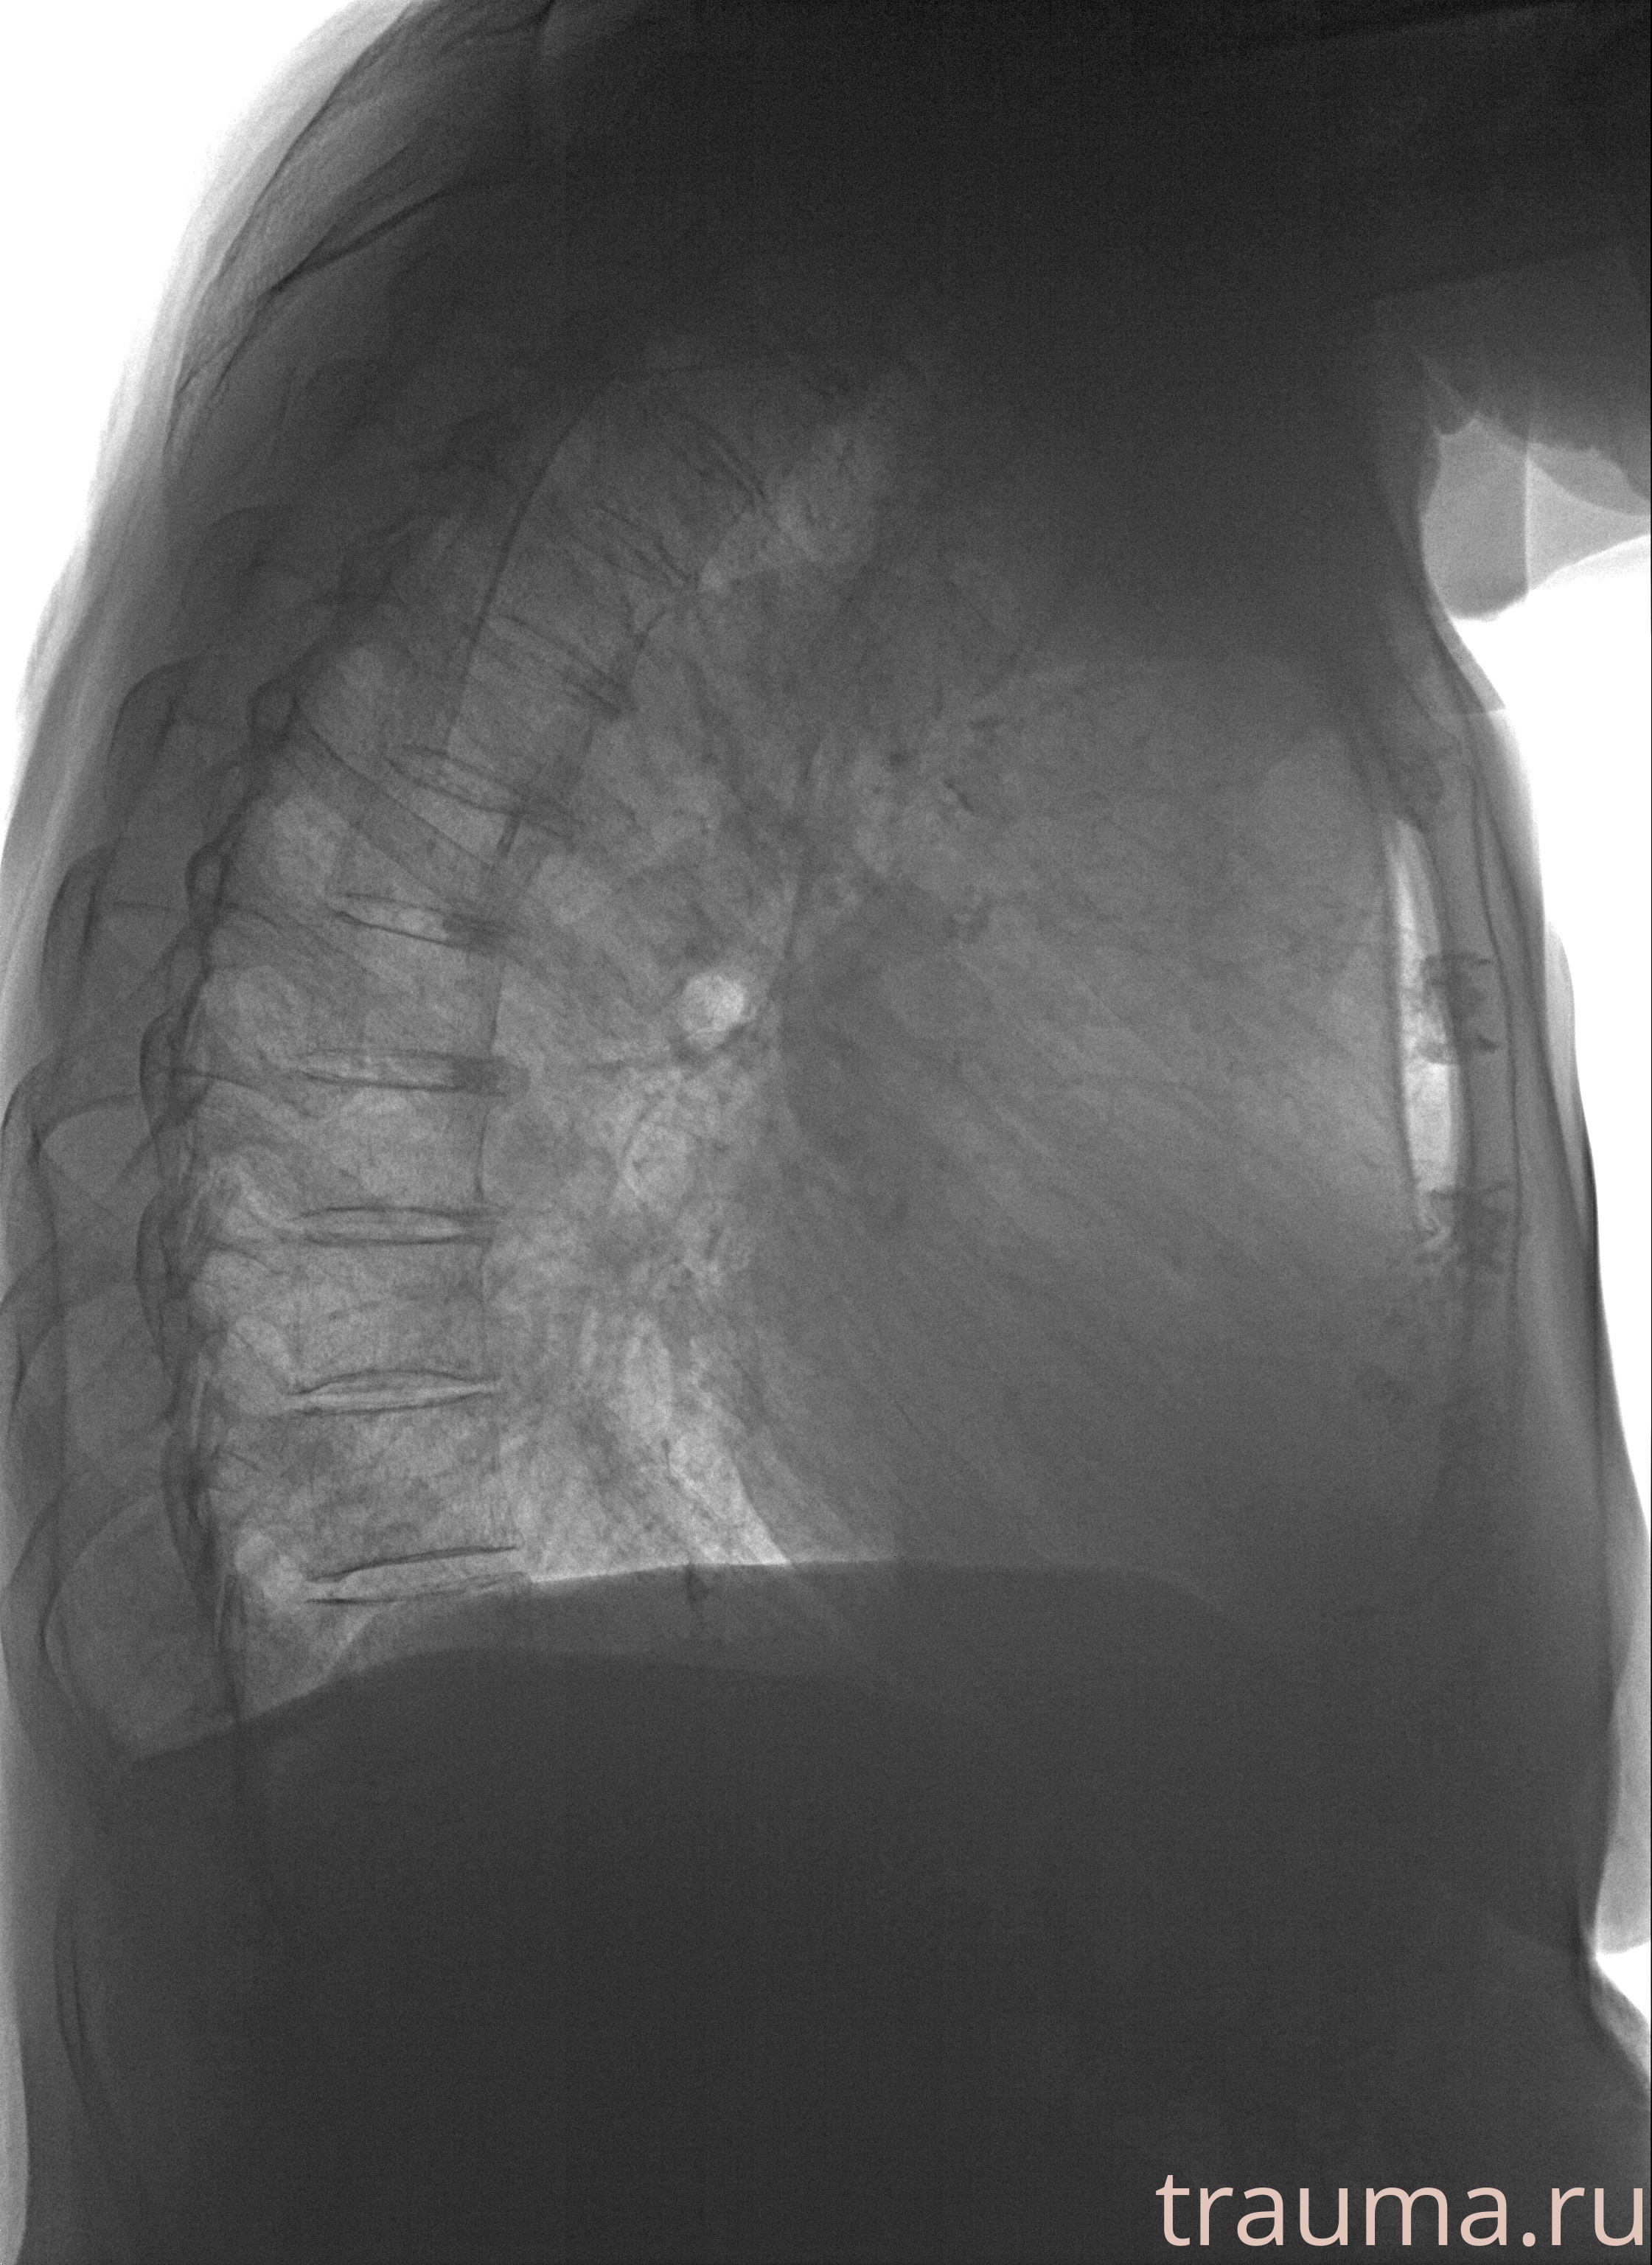

Рентгенограммы

Рентген на дому: по вашему адресу приезжает врач-рентгенолог, травматолог-ортопед с мобильным рентгеновским аппаратом, проводит диагностику травмы или заболевания, делает необходимые рентгенограммы, дает рекомендации по дальнейшему лечению. Получить качественные снимки в домашних условиях возможно благодаря уникальной методике, разработанной МосРентген Центром для института  Склифосовского

при переломе шейки бедра и пневмонии от компании МосРентген Центр - партнера Института имени Склифосовского